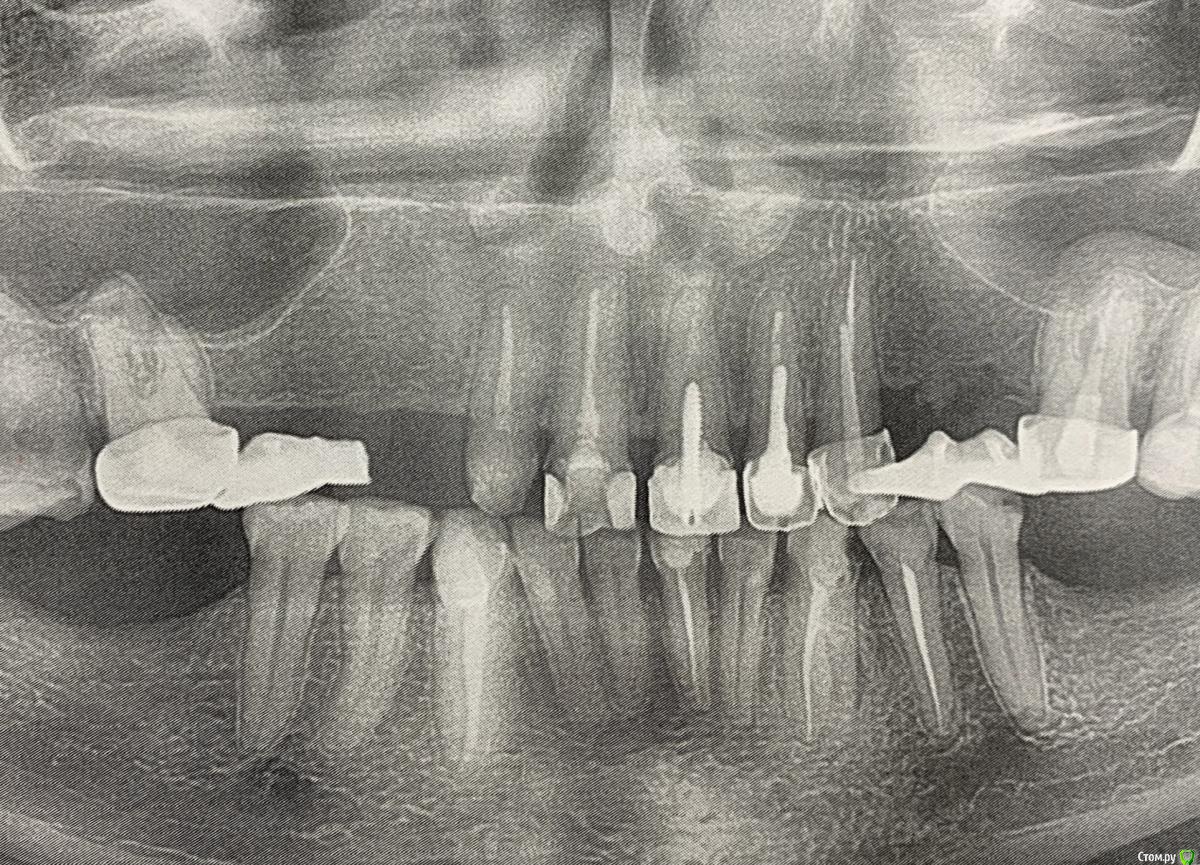

LeninK Опубликовано 8 августа, 2019 Поделиться Опубликовано 8 августа, 2019 (изменено) Здравствуйте. стоял мост на 2-6 зуб (нет 3,4,5) сверху, мост простоял 15 лет, потом сломался, поставили временный, но тот спал и часть зуба сломалась, (двойка) возможно сильно обточил врач зуб. Разные врачи предлагают все по разному, нужен совет. 1) вариант: на 1,2 и 6 одеть мост полуполковник как бы из металкерамики, учитывая вкладку в зуб 2. 2) вариант: на 2,1,1,2 поставить коронки!металкерамика, на 6 цельнолитой, и на 3,4,5 съемный протез типа бабочки( не помню точное название). Подскажите какой вариант лучше Изменено 8 августа, 2019 пользователем LeninK Ссылка на комментарий

LeninK Опубликовано 9 августа, 2019 Автор Поделиться Опубликовано 9 августа, 2019 К сожалению имплантацию не хочу, там пазухи носа или что то такое , близко, что осложняет все. Ссылка на комментарий